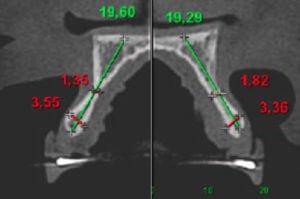

iniciou-se a avaliação do leito cirúrgico a ser implantado. As imagens da Tomografia evidenciaram uma atrofia importante da espessura,

comum aos pacientes de agenesia, que não possuem o desenvolvimento natural do rebordo alveolar pela ausência do dente permanente. Um procedimento cirúrgico foi realizado para regenerar o rebordo alveolar por vestibular e por palatino, com técnica de regeneração óssea guiada ,utilizando-se osso autógeno coletado do mento, associado a matriz inorgânica de osso bovino, e recoberto com membrana colágena fixada com micro parafusos.

Após 9 meses, imagens tomográficas evidenciam o volume alcançado com o procedimento reconstrutivo,